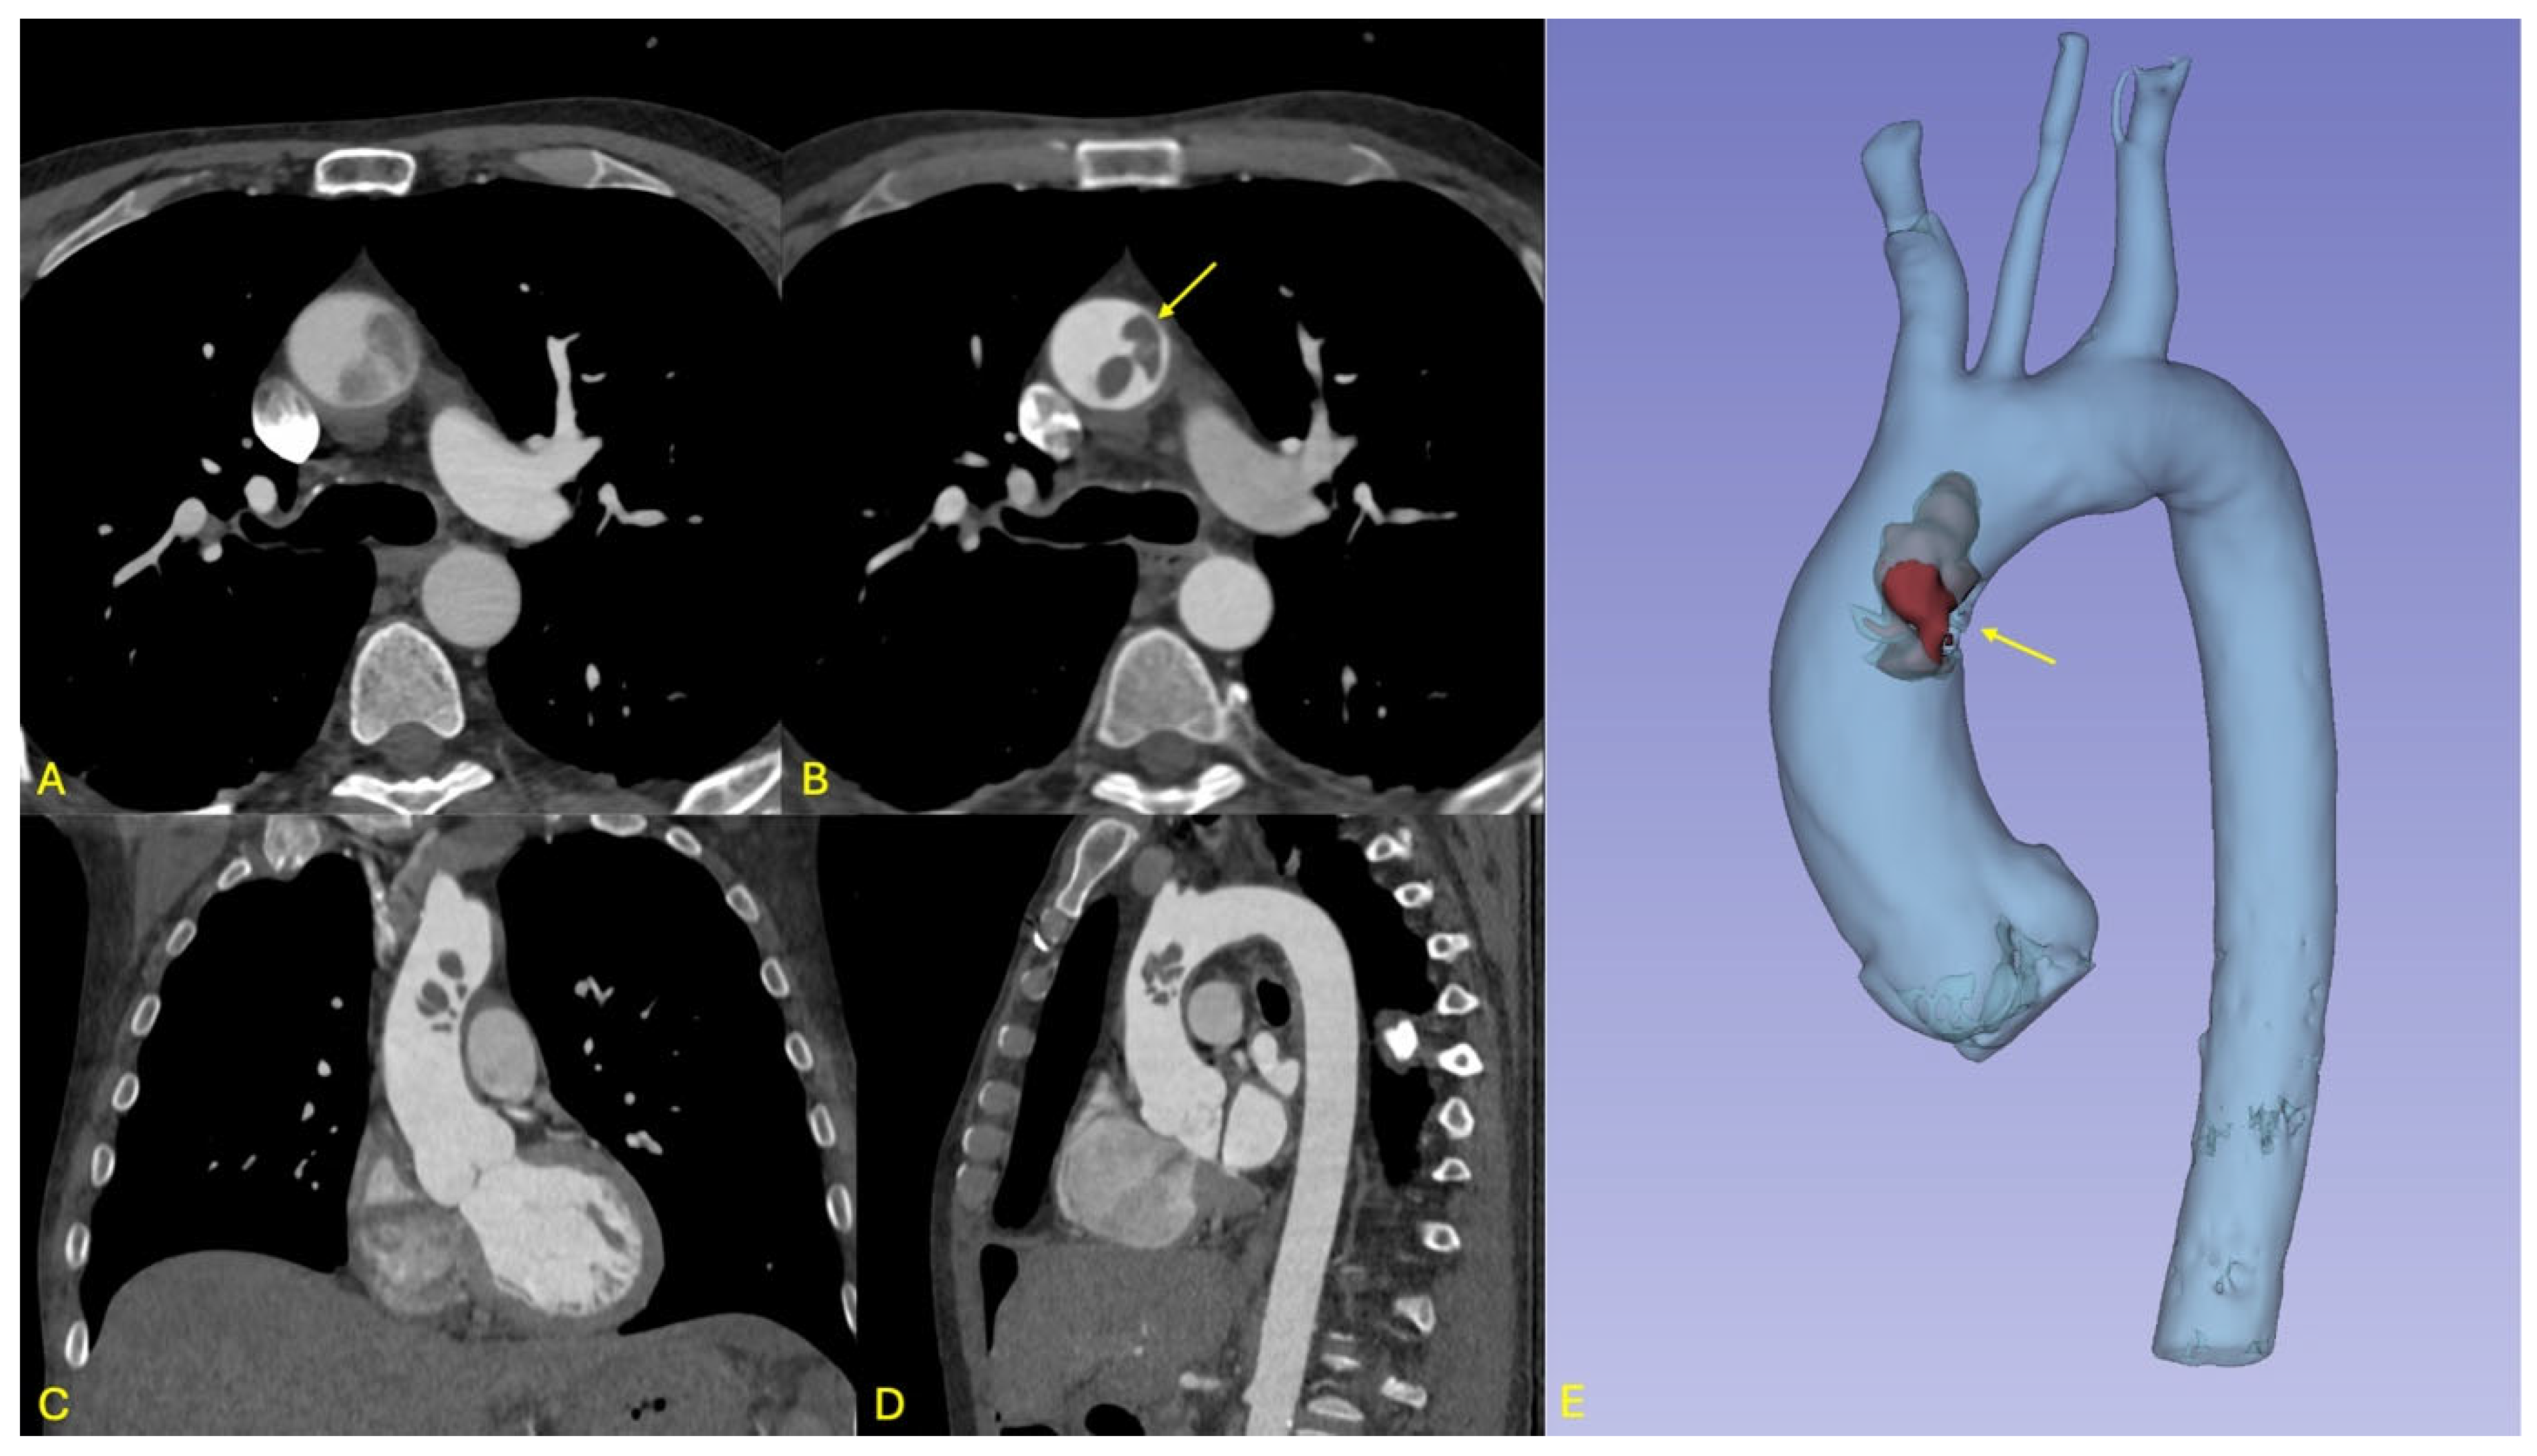

Figure 3. Overview of initial and follow-up imaging findings in patient 2. (A): Diffusion-weighted MRI sequence displayed in oblique coronal view showing multiple dot-like cortical hyperintensities of the posterior and pre-central regions (arrows), consistent with embolic stroke. (BD): Axial and sagittal views as well as 3D multiplanar reconstruction from the initial ECG-gated CT angiography of the aorta, showing an endoluminal thrombus attached to a soft-plaque (arrow) of the anterior aspect of the ascending aorta and bulging into the aortic lumen. (E): Axial view from the initial aortic CT angiography showing a second, more tubular thrombus of the subrenal aorta (arrow). (F): Follow-up CTA showing regression of the thrombus in the ascending aorta, as well as two new thrombi (arrows), in front of the isthmus and at the thoraco-abdominal junction; the subrenal thrombus had resolved.

Brain magnetic resonance imaging (MRI) demonstrated multiple acute ischemic lesions involving both supratentorial and infratentorial regions, with some foci exhibiting hemorrhagic transformation. The distribution of lesions across multiple vascular territories was suggestive of an embolic etiology, although the exact timing of the ischemic events remained unclear (see Figure 3).

Initial non-contrast CT imaging incidentally revealed a floating thrombus within the aortic arch, prompting further evaluation with an urgent contrast-enhanced CT angiography. The angio-CT confirmed the presence of a stable, mobile thrombus located in the distal ascending aorta (see Figure 3). Additionally, the scan identified a small ulcerated atherosclerotic plaque in the abdominal aorta just proximal to the origin of the celiac trunk, as well as a second floating thrombus in the subrenal segment of the abdominal aorta. No evidence of ischemia was detected in the solid intra-abdominal organs, and the splanchnic arterial branches remained patent.